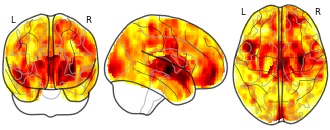

License information was derived automaticallyArea coveredNorth CarolinaDescriptionA collection of 1 brain maps. Each brain map is a 3D array of values representing properties of the brain at different locations.

License information was derived automaticallyArea coveredNorth CarolinaDescriptionCollection description

Structural MRI

2nd-order rule acquisition

T

License information was derived automaticallyDescriptionBackground and purposeArterial spin-labeling (ASL) was recently introduced as a noninvasive method to evaluate cerebral hemodynamics. The purposes of this study were to assess the ability of ASL imaging to detect crossed cerebellar diaschisis (CCD) in patients with their first unilateral supratentorial hyperacute stroke and to identify imaging or clinical factors significantly associated with CCD.Materials and methodsWe reviewed 204 consecutive patients who underwent MRI less than 8 hours after the onset of stroke symptoms. The inclusion criteria were supratentorial abnormality in diffusion-weighted images in the absence of a cerebellar or brain stem lesion, bilateral supratentorial infarction, subacute or chronic infarction, and MR angiography showing vertebrobasilar system disease. For qualitative analysis, asymmetric cerebellar hypoperfusion in ASL images was categorized into 3 grades. Quantitative analysis was performed to calculate the asymmetric index (AI). The patients’ demographic and clinical features and outcomes were recorded. Univariate and multivariate analyses were also performed.ResultsA total of 32 patients met the inclusion criteria, and 24 (75%) presented CCD. Univariate analyses revealed more frequent arterial occlusions, higher diffusion-weighted imaging (DWI) lesion volumes and higher initial NIHSS and mRS scores in the CCD-positive group compared with the CCD-negative group (all p < .05). The presence of arterial occlusion and the initial mRS scores were related with the AI (all p < .05). Multivariate analyses revealed that arterial occlusion and the initial mRS scores were significantly associated with CCD and AI.ConclusionASL imaging could detect CCD in 75% of patients with hyperacute infarction. We found that CCD was more prevalent in patients with arterial occlusion, larger ischemic brain volumes, and higher initial NIHSS and mRS scores. In particular, vessel occlusion and initial mRS score appeared to be significantly related with CCD pathophysiology in the hyperacute stage.